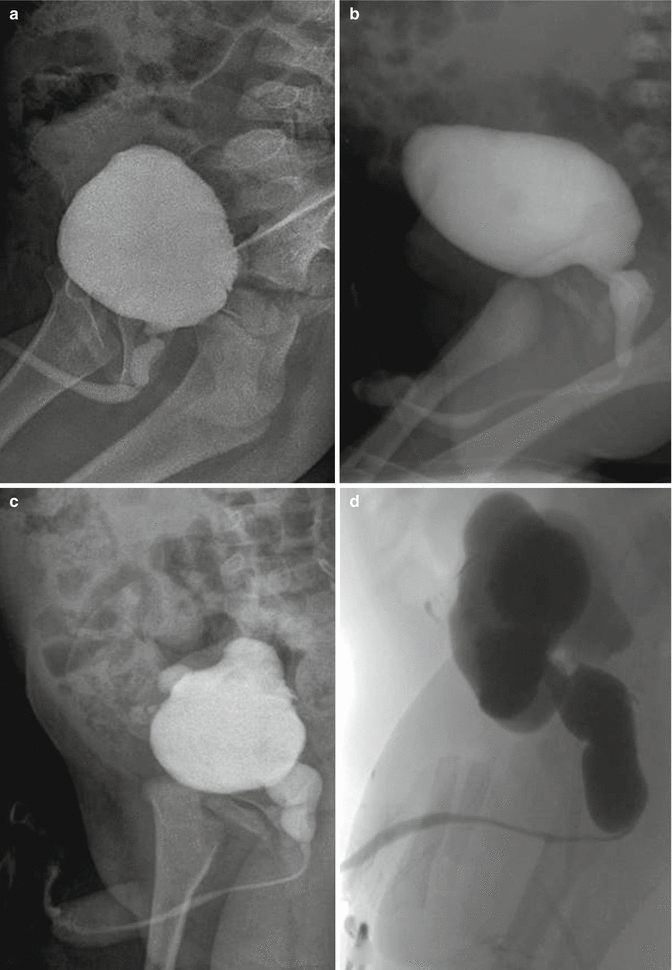

Download Posterior Urethral Valves Radiology PNG. Posterior urethral valve (puv) disorder is an obstructive developmental anomaly in the urethra and genitourinary system of male newborns. A posterior urethral valve is an abnormal congenital obstructing membrane that is located within problems resulting from the presence of a posterior urethral valve are depicted in the image below.

Membranous tissue in the posterior urethra results in varying degrees of obstruction. Posterior urethral valves consist of a thin membrane of tissue (fig 1) that is the most common cause of lower urinary tract obstruction in male infants, occurring in between 1 in 8000 to 1 in 25 000 live births.1 posterior urethral valves affect both the upper and the lower urinary tract. Puv are also the most common cause of chronic.

The most common cause of lower urinary tract obstruction in male infants is posterior urethral valves.

Posterior urethral valve disorder is an obstructive developmental anomaly in the urethra and genitourinary system of male newborns. Posterior urethral valves (puv) are obstructive membranes that develop in the urethra (tube that drains urine from the bladder), close to the bladder. Posterior urethral valves (puvs) was first described from hugh hampton young in 1919 (1). The left kidney displays normal uptake and excretion of nuclear tracer.